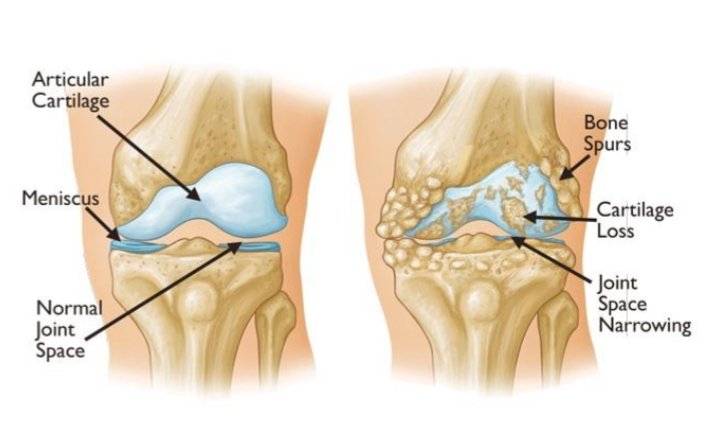

Osteoarthritis, commonly known as wear-and-tear arthritis, is a condition in which the natural cushioning between joints — cartilage — wears away. When this happens, the bones of the joints rub more closely against one another with less of the shock-absorbing benefits of cartilage. The rubbing results in pain, swelling, stiffness, decreased ability to move and, sometimes, the formation of bone spurs.

- X-rays, which can show bone and cartilage damage as well as the presence of bone spurs